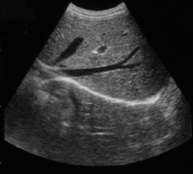

高清晰图像: